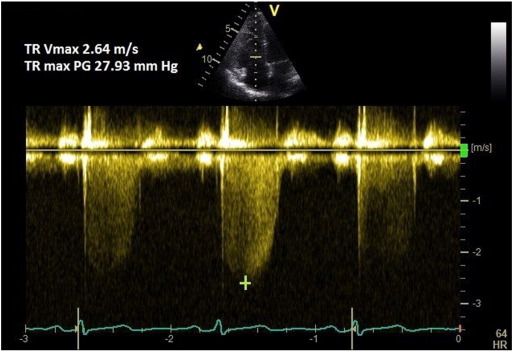

Continuous wave (CW) Doppler of the tricuspid regurgitation (TR) trace is used to measure the difference in pressures between the right ventricle and right atrium. The simplified Bernoulli equation (P = 4[TRmax]2 ) is used to calculate this pressure difference using peak TR velocity. This method correlates well with PASP on right heart catheterisation [6] and [7] . A peak TR velocity value of ≤ 2.8 m/s is considered normal.

A coaxial TR jet is identified in parasternal long axis (RV inflow), parasternal short axis, or apical 4-chamber view with the help of colour Doppler. CW Doppler is used with a sweep speed of 100 mm/s to achieve a satisfactory envelope (Fig. 1 ). The peak velocity of the envelope is then measured (TRmax ). A value of ≤ 2.8 m/s suggests low probability, a value of 2.9–3.4 m/s indicates intermediate probability, and a value > 3.4 m/s suggests a high probability for pulmonary hypertension [1] . Traditionally, right atrial pressure (RAP) is assumed by the size and distensibility of inferior vena cava (IVC) during inspiration at rest and during forced inhalation, and this value is added to the peak TR velocity [8] . However, recent ESC guidelines suggest just using the TRmax without additional RAP, as IVC assessment is error prone [1] . Mean PAP can be approximated from the systolic PAP (SPAP) using the following formula: mPAP = 0.61*SPAP + 2 mmHg [9] .

Fig. 1. TR Vmax method for measuring PASP. |

If there is marked sinus arrhythmia, the trace should be obtained at expiratory apnoea. If the patient is in atrial fibrillation, then 8 consecutive TR velocities are averaged to give the best estimate [7] . In case of pulmonary valve or right ventricular outflow tract (RVOT) stenosis, this method overestimates the PASP; then the peak pressure gradient across the valve or RVOT should be subtracted from the measured PASP.

A lesser degree of TR may occur in a compensated right ventricle (due to elevated ventricular pressure) and this could lead to underestimation of PASP. Similarly, severe TR could cause equalisation of right atrial and ventricular pressures which may cause the TR Doppler envelope to be cut short, leading to underestimation of PASP (Fig. 2 -C) [8] . RAP is often overestimated if IVC measurement is used, leading to overestimation of PASP [10] . Calculations using the TR trace assume that there is no pulmonary valve stenosis and may be inaccurate in the presence of RV systolic dysfunction. TR signal could be poor in a good proportion of patients with lung disease, and TRmax measurement should be avoided in the absence of a good Doppler envelope (Fig. 2 ) [11] .